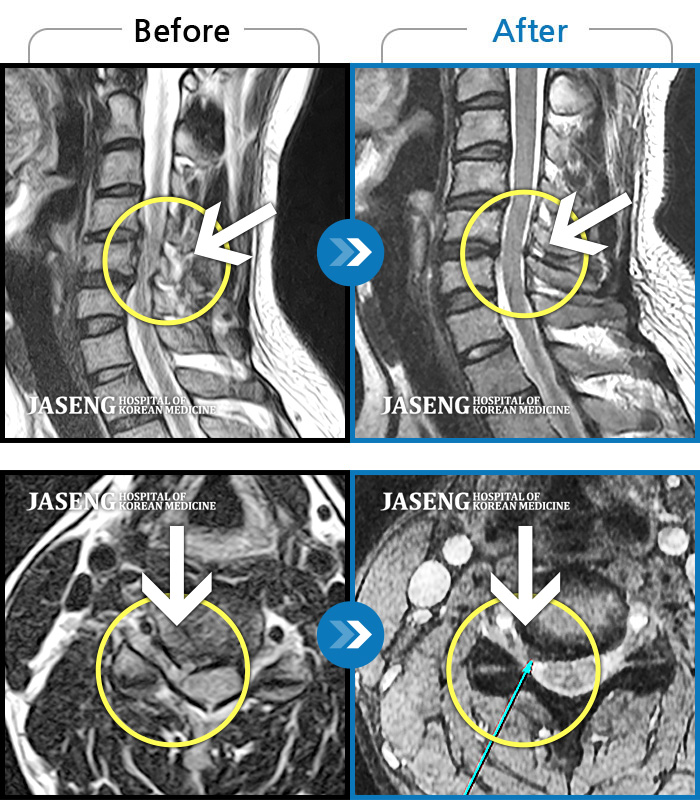

Before

After

환자에게 사전 동의를 받아 동일 조건에서 촬영되었습니다.

개인에 따라 치료 후 부작용이 발생할 수 있으니 의료진과 상담 후 치료를 진행하시기 바랍니다.

좌측 둔부 통증 및 좌측 하지 통증

허리 양측과 우측 둔부 통증, 좌측 하지 후면으로 저림